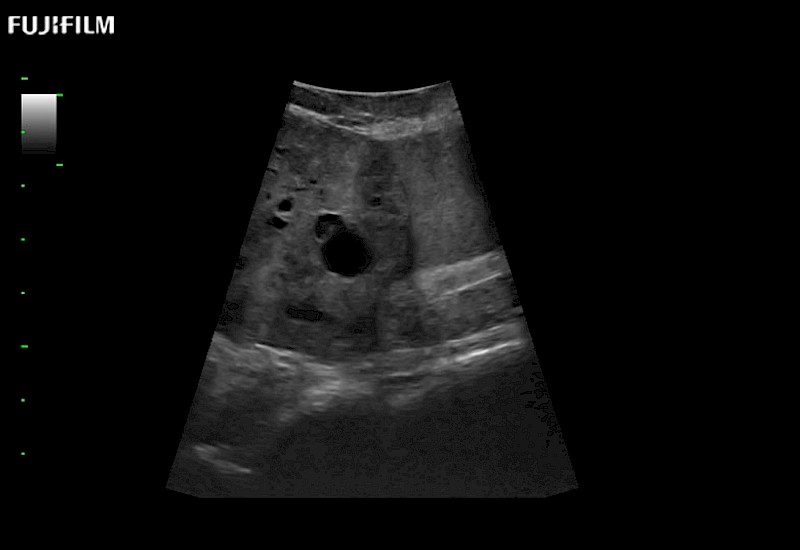

Curved array 4-way laparoscopic transducer for better visualization of targeted lesions.

Exclusive linear array 4-way laparoscopic transducer for better visualization of targeted lesions.

Exclusive linear array rigid laparoscopic transducer for better visualization of targeted lesions.